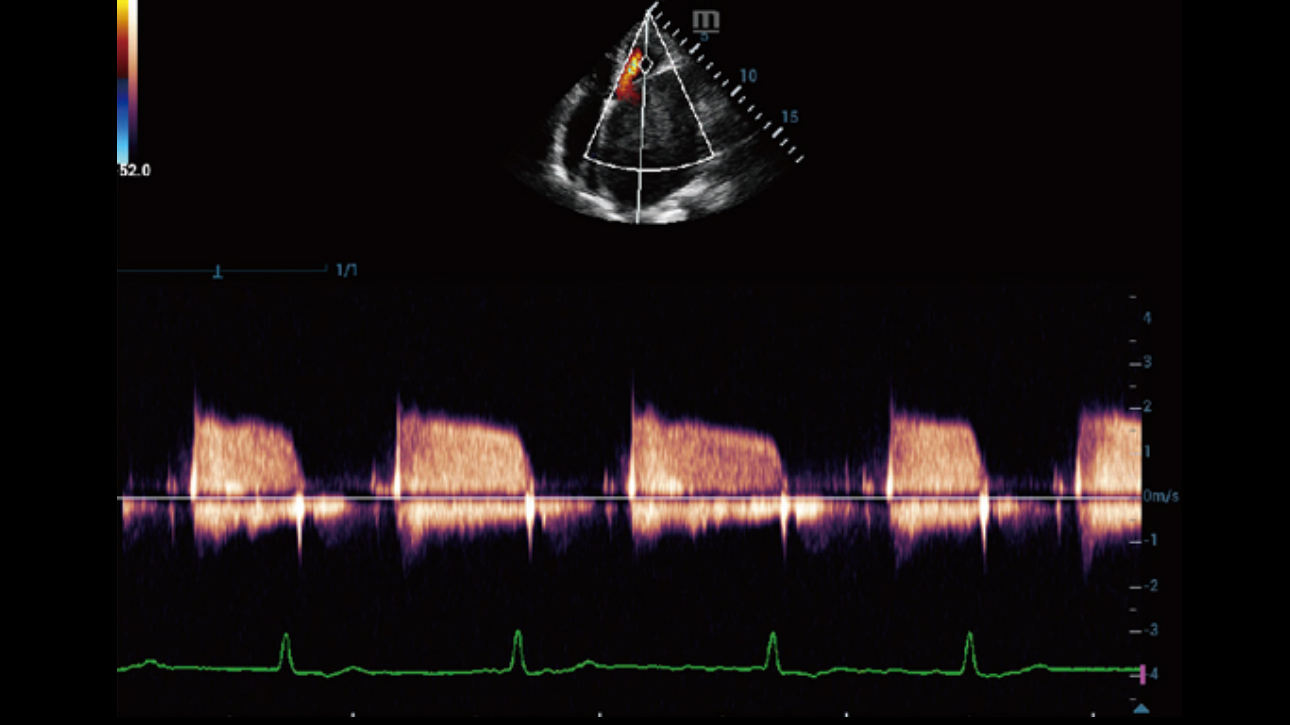

Dynamic Pixel Focusing technology allows the Resona 6 to achieve extreme uniformity in pixel level throughout the whole field of view. Now there's no need to adjust the focal positions to achieve uniformity across patient exams.

Channel data based ZST+ provides Enhanced Channel Data Processing for greatly improved imaging clarity. By multiple and retrospective channel data processing, it makes the best use of acoustic information for image improvement.

HD Scope: By processing channel data retrospectively, HD Scope enables tissue-specific enhancement with improved detailed information and image contrast on specific region of interest.